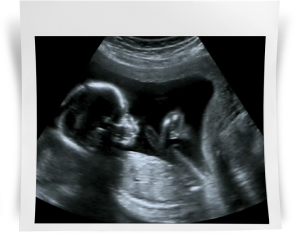

Вы продолжаете посещать вашего доктора в женской консультации, в зависимости от вашего возраста и состояния здоровья через 2-3 недели, сдаете общий анализ крови и общий анализ мочи. Совсем скоро наступит время второго УЗИ скрининга, и вы сможете увидеть вашего подросшего малыша, который выглядит уже совсем как настоящий новорожденный.